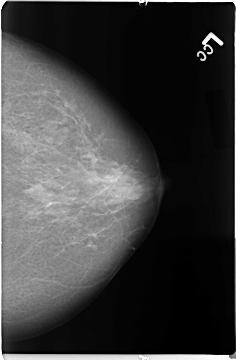

B_3098_1.RIGHT_CC

RIGHT_CC LINES 4632 PIXELS_PER_LINE 2744 BITS_PER_PIXEL 12 RESOLUTION 50 OVERLAY

FILE: B_3098_1.RIGHT_CC.OVERLAY

TOTAL_ABNORMALITIES 1

ABNORMALITY 1

LESION_TYPE MASS SHAPE OVAL MARGINS CIRCUMSCRIBED

ASSESSMENT 3

SUBTLETY 3

PATHOLOGY BENIGN

TOTAL_OUTLINES 1

BOUNDARY